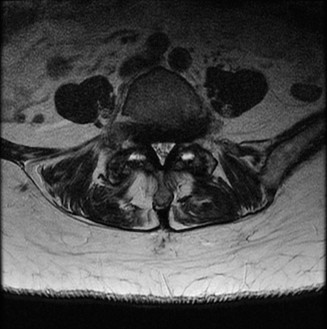

Figure 1–2

The correct answer is (B). The clinical scenario describes a patient with central cord syndrome (CCS). CCS continues to be the most common incomplete spinal cord injury accounting for 15.7% to 25% of all spinal cord injuries. The characteristic presentation is an extension moment injury in a previously spondylotic and stenotic spine. Figures 1–1 to 1–3 demonstrate a spondylotic spine with central narrowing and CSF effacement that is worst at the C3–4 level. Bleeding, edema, and/or Wallerian degeneration lead to damage of the lateral corticospinal tract which is the main descending motor tract in the spinal cord. The more central anatomic position of the homunculus to the upper extremities places them at greater risk than those to the lower extremities. As such, injury to the lateral corticospinal tract is characterized by upper more than lower extremity involvement and motor deficits being more pronounced than sensory deficits.